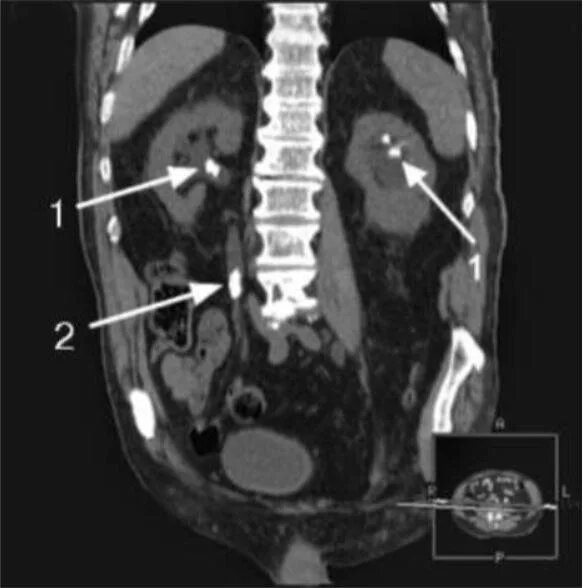

Кт мочевыводящих путей